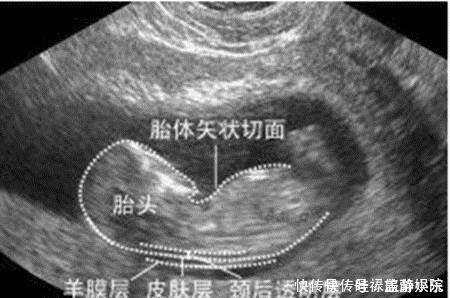

检查时间:怀孕早期到怀孕中期,一般在孕12周产检时检查。这项检查大概在孕11周6天时开始检查,又称为“胎儿颈透明膜厚度的检查”,这项检查对检查时间有严格要求,因而孕妈要提前预约好,按时去做检查。检查方法:通过B超来测量胎儿颈部后方透明膜的厚度,来初步判断胎儿神经管发育的情况,是否存在畸形。如果透明膜过厚,就可能提示:胎儿存在神经管发育的畸形。

京妈建议:① 由于NT检查是最早的关于胎儿智力方面的筛查,因此孕妈一定要严格把控时间做好孕检,及时了解胎儿发育的情况;② NT检查是通过B超来进行的,而且可能是在第一次正规产检时做,不少孕妈会紧张,不过还是建议孕妈尽量避免紧张焦虑,积极配合好医生的检查;③ 如果检查的结果显示:胎儿颈透明膜厚度过厚,孕妈要及时和医生沟通,听从医生的意见。